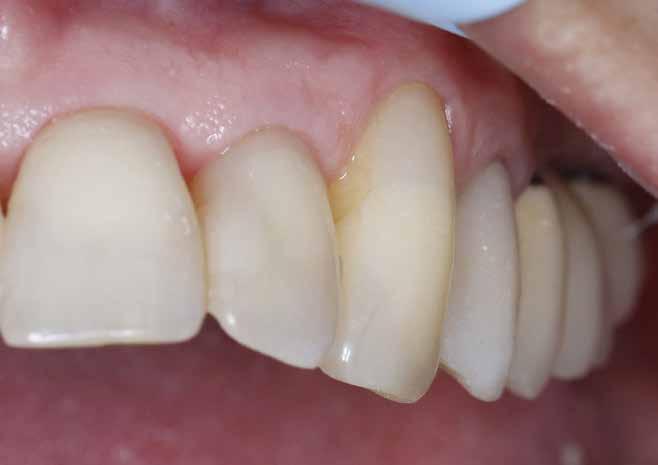

A 2020 januárjában elkezdett kezeléssorozat befejezését az év márciusában, hazánkba is begyűrűző Covid-19 pandémia késleltette, így kb. 6 hónap gyógyulás után láttunk hozzá az emergencia profil és a gingivális zenit ideiglenes koronával történő formázásához (11. és 12. kép). A 3 hetente végzett apró alakításokkal sikerült megfelelő ínyprofilt kialakítani, a „rózsaszín esztétika” a páciens számára is megfelelő volt. A bal felső nagymetsző fog meziális kompozit tömés cseréjét követően, individualizált nyitott kanalas lenyomati fejet készítettünk: az akrilát ideiglenes korona profilját átlátszó szilikonnal lemásoltuk, majd a körszimmetrikus gyári lenyomati fej és az ideiglenes korona kontúrja közötti hézagot folyékony kompozittal töltöttük ki (13. kép). Az így készített egyéni lenyomati fejjel vettünk lenyomatot a végleges, kerámialeplezésű cirkónium-dioxid vázas, átmenő csavaros rögzítésű koronához. (A fogtechnikai munkát Nébl Péter fogtechnikusmester készítette.), (14., 15., 16 és 17. képek).

A kész korona átadásakor a páciens elégedett volt az esztétikával, az azóta eltelt évben rendszeres kontrollokon jelent meg, melyek során meggyőződtünk a kemény- és lágyszövetek stabilitásáról (18. és 19. képek).

17. a–b képek: A kész munka átadáskor. 18. a–c képek: 1 éves kontroll. 19. kép: Intraorális kontroll röntgen felvétele 1 évvel az átadás után.